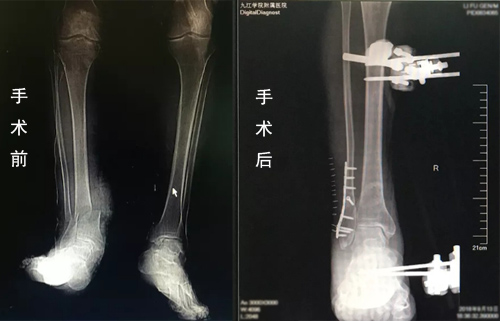

近日,临床医学院/附属医院骨科显微外科团队成功完成一例高龄小腿离断伤再植手术。目前患者恢复良好,生命体征平稳。

临床医学院/附属医院显微外科医护团队与麻醉科、手术室、输血科等进行了充分的术前讨论,制定好周密的麻醉及手术方案。由许刚主治医师主刀,赵斌副主任医师,赵庆飞、刘秭洋医师共同为患者实施了右小腿离断伤再植术。经过4个多小时的艰苦奋战,手术顺利完成小腿骨折、血管、神经、肌腱及皮肤的修复。术后由科室护理团队制定了详细的护理计划,严密观察患者生命体征及切口情况,全程进行细致护理。通过科室全体医护人员的共同努力,李大爷术后恢复各项指标良好。

据李军副主任介绍,断肢再植是一个体现医院显微外科能力的标志性手术。此患者受伤后断肢从表面上看有少量皮肤和肌肉组织将断肢与机体相联,但实际上这部分离断肢体已无血液供应和神经支配,已成为毫无活力的组织,这为再植手术的成功增加了难度;另外,老年患者的血管条件不好,是再植的又一个难点。此次手术用到了血管搭桥技术和神经束的吻合,手术难度系都数非常高,尤其是患者处于失血性休克状态,对医师的要求就更高。